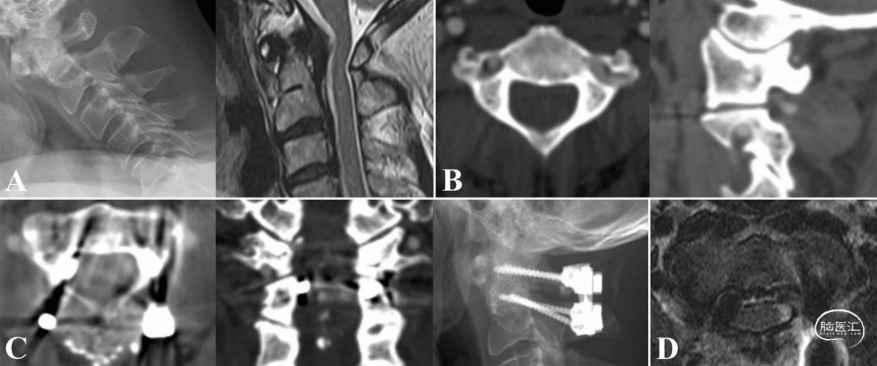

图2. 病例1,67岁男性,枕部疼痛、手部笨拙和步态障碍症状。A. 术前影像学显示寰枢椎不稳和齿状突后假瘤导致的脊髓受压。B. 在右侧椎弓根置入椎弓根螺钉时,发现HRVA和椎弓根狭窄,椎动脉损伤的风险很高。C. 采用C2MWS方法置入螺钉。D. 螺钉置入椎管内,未发生脊髓损伤和神经功能障碍。术后MRI显示脊髓无损。